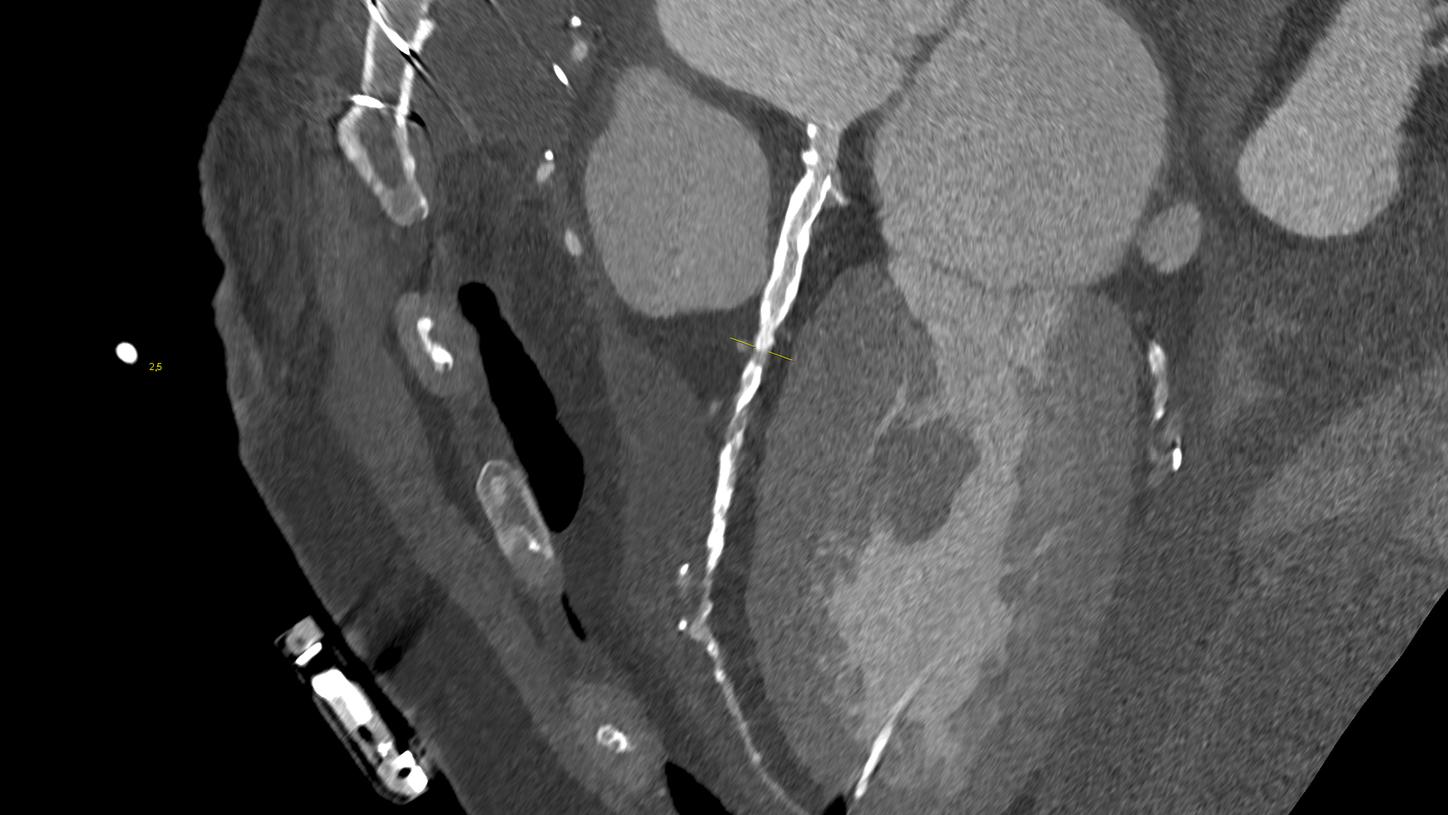

At the heart of NAEOTOM Alpha® is a radically new photon-counting detector. The QuantaMax detector directly converts X-rays into an electrical signal, which is then used to create an image. The energy of each X-ray is measured, so spectral information is available for every scan, and the images are contrast-rich with high spatial resolution at the same dose. Combining the high spatial resolution of the QuantaMax photon-counting detector with our Dual Source temporal resolution enables the visualization of fine details for increased diagnostic confidence.